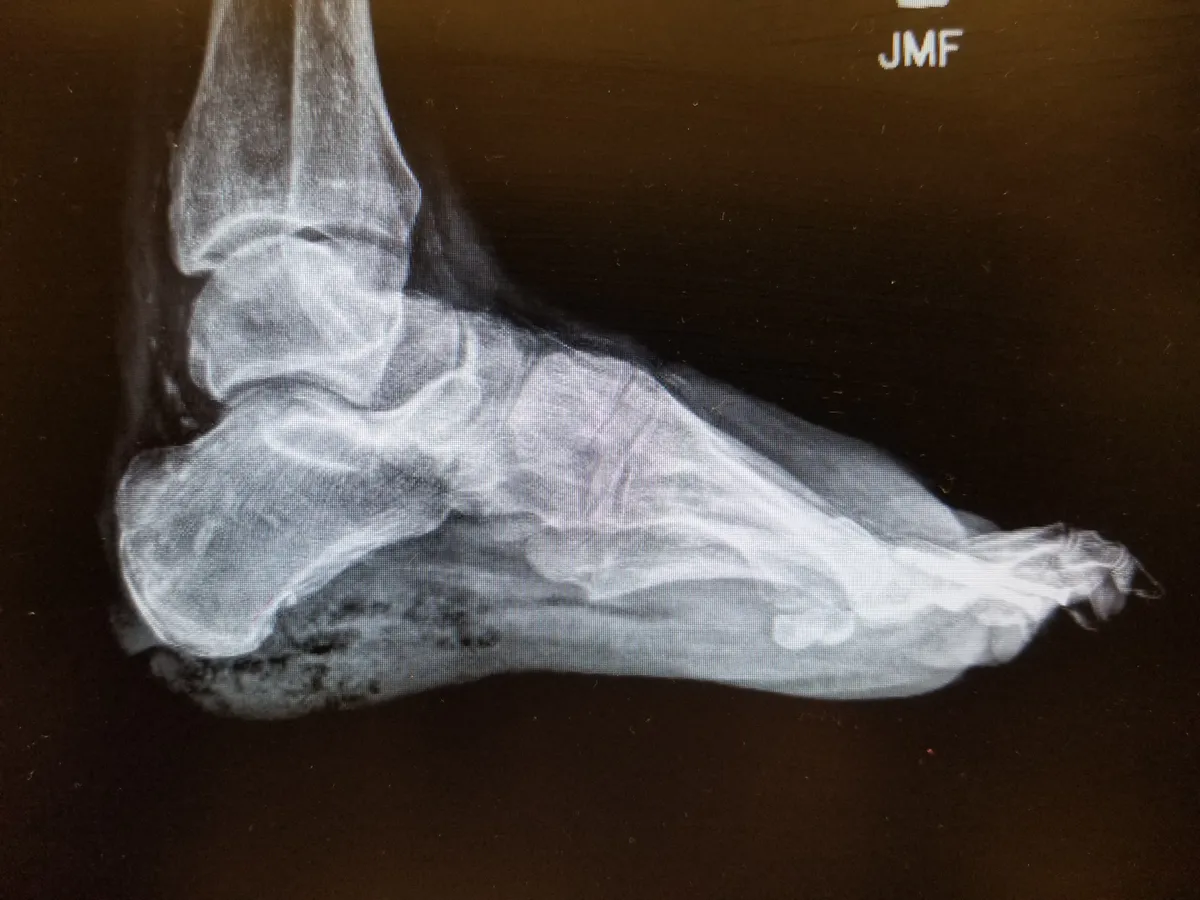

A diagnózis fizikális vizsgálaton, vérvizsgálaton, érultrahangon vagy képalkotó eljárásokon alapul. A cél annak megállapítása, hogy mennyire súlyos a keringési zavar, van-e fertőzés, és még megmenthetők-e az érintett szövetek.